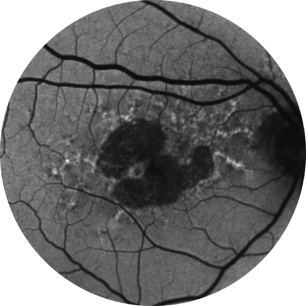

Autofluorescência de fundo de olho normal de uma retina

A angiografia por autofluorescência do fundo ocular é, atualmente, uma tecnologia de imagem padrão para visualizar o epitélio pigmentar da retina (EPR) na atrofia geográfica.16